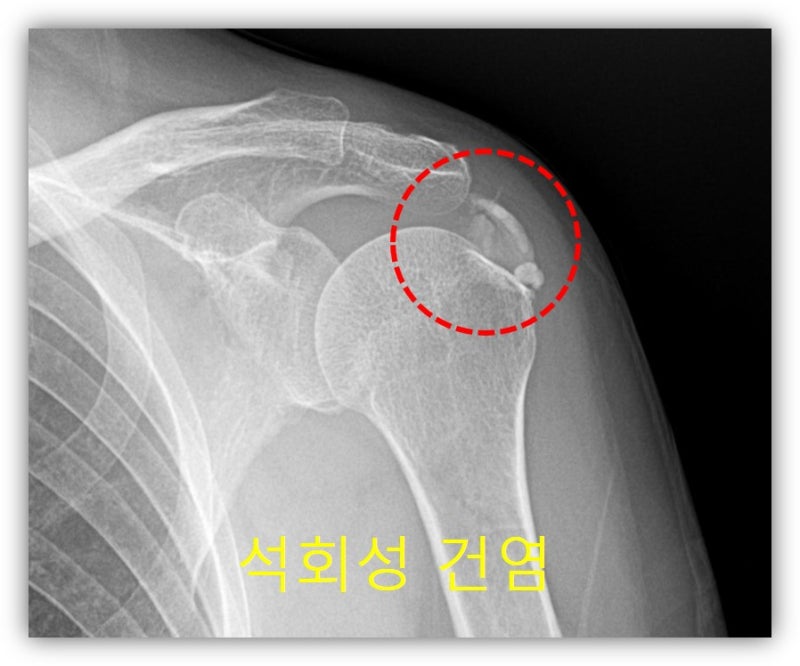

안녕하세요. 이번에는 석회성 건염으로 병원을 내원하신 환자에게 뉴핌스 치료를 한 사례를 보여드리겠습니다. 66세 여자 환자 분으로 6개월간 좌측 어깨 통증이 심하게 있으셨고 타 병원에서 아플때 주사만 맞았던 환자 였습니다. 최근들어 통증이 너무 심해져서 내월 2일 전에도 타병원에서 주사를 맞았으나 전혀 호전이 안되어 저한테 내원하였습니다. 통증이 너무 심하여 이학적 검사를 하지 못했고 x-ray 상 어마어마한 석회성 건염이 관찰되었습니다.

석회가 아주 큰 경우, 그리고 오래된 경우 회전근개의 손상이 있을 가능성이 있어 MRI 검사도 시행하였습니다.